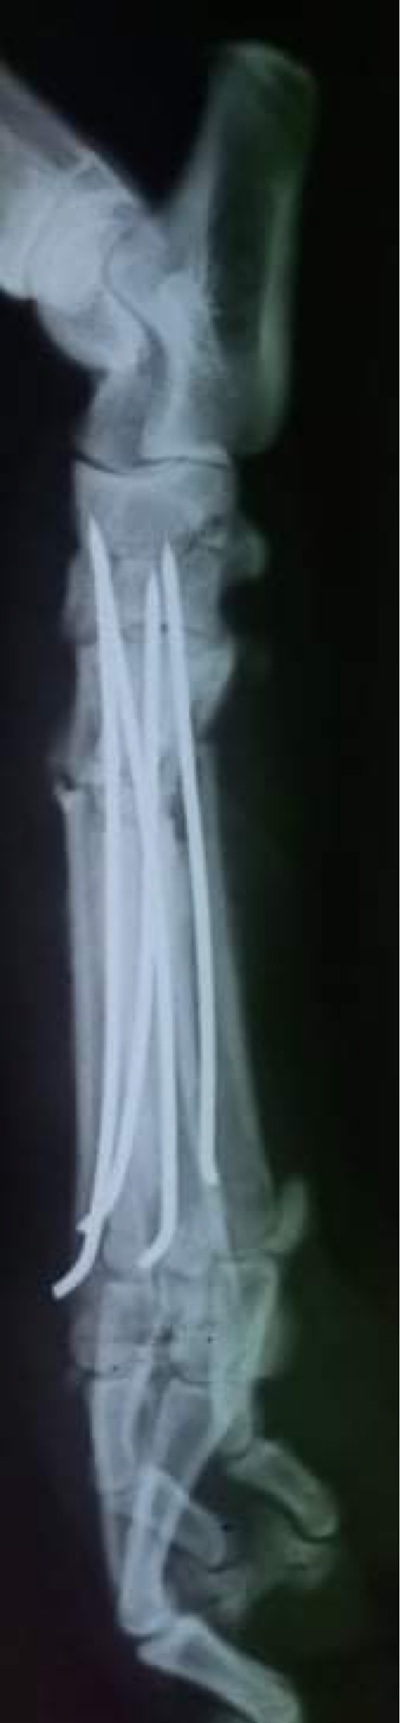

Mittelfußfraktur - OP am 22.11.2021

BRADLEY hat die OP gut überstanden und hat am 03. Dezember 2021 die Klinik verlassen können und ist bis zum Transport am 11. Dezember 2021 auf einer französischen Pflegestelle.